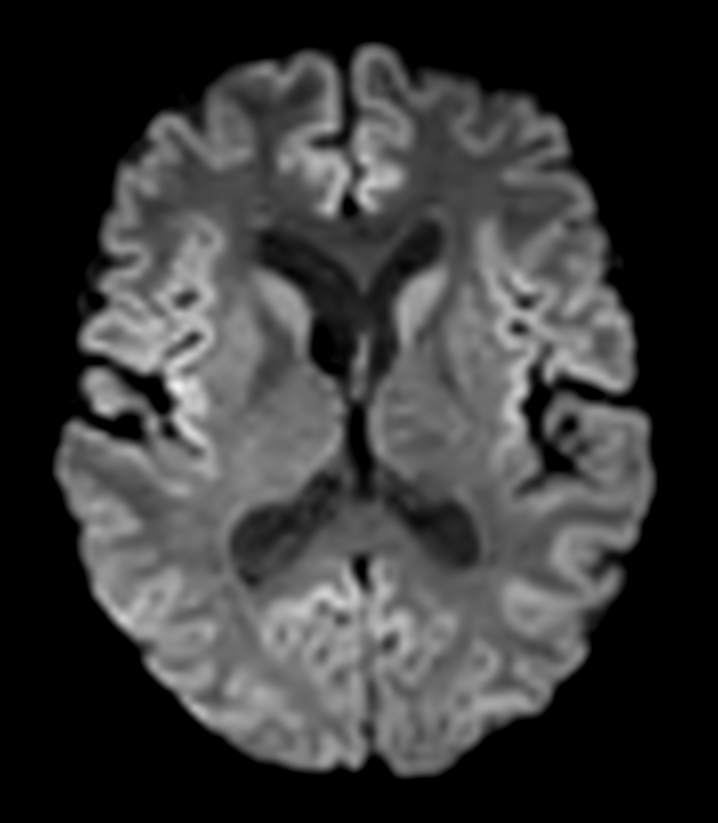

DWI b1000